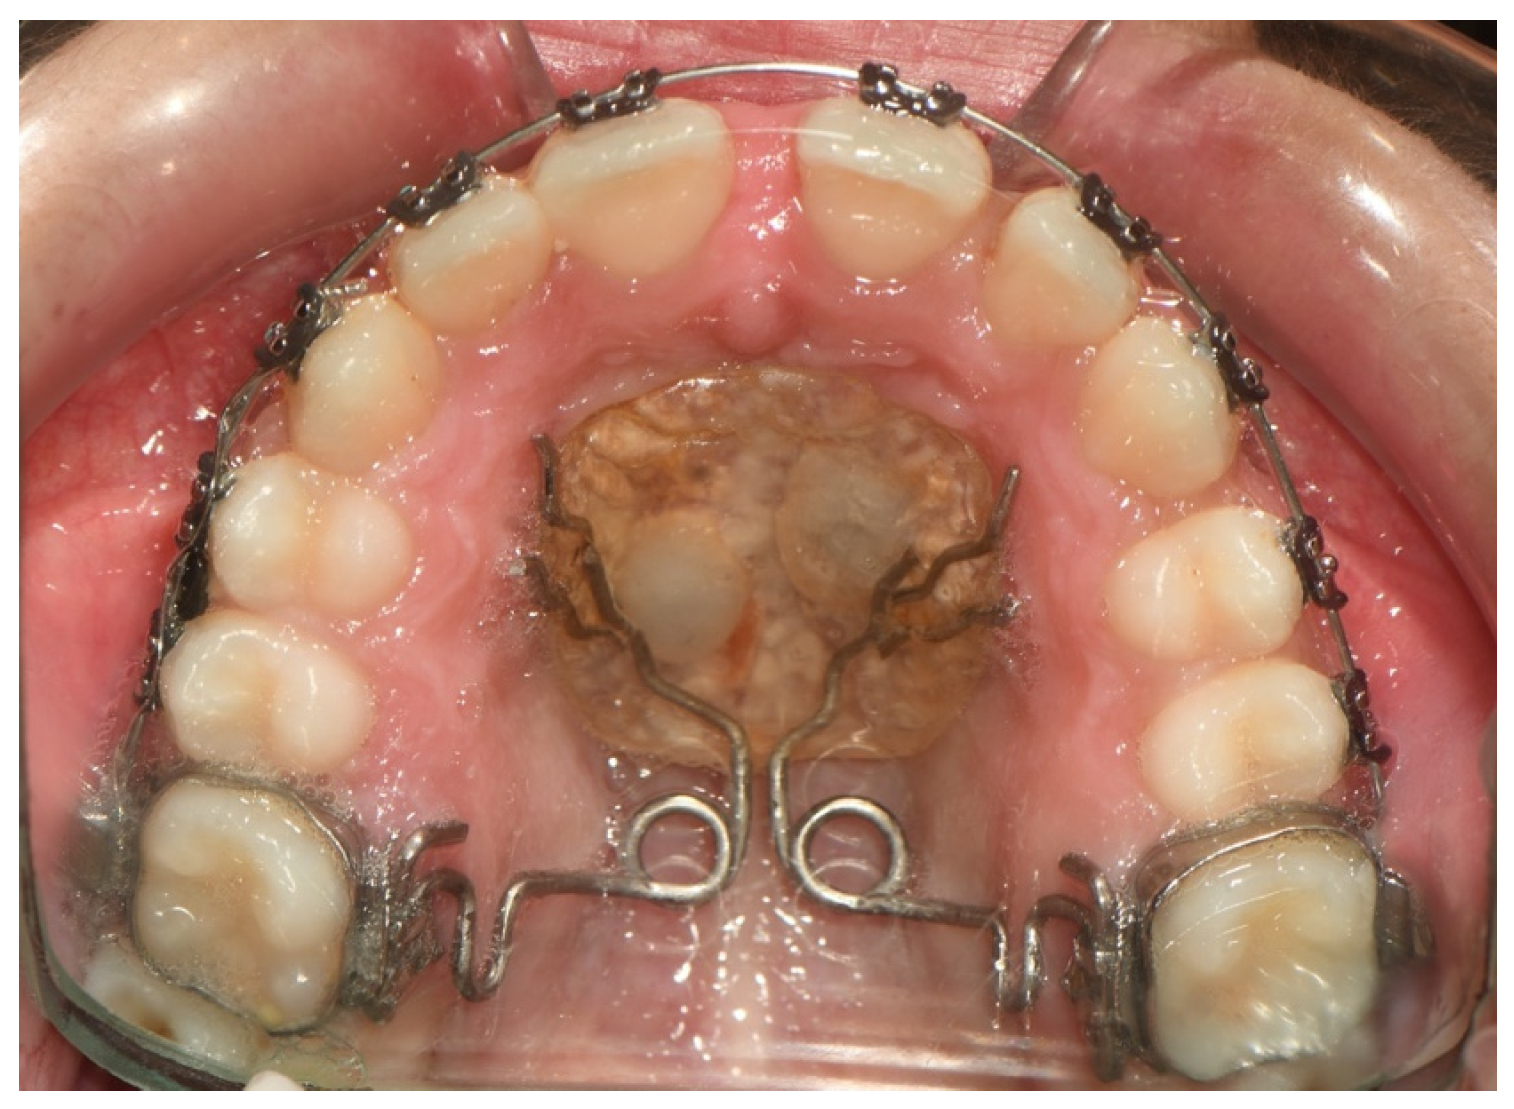

Modified Pendulum Appliance

| Kircelli et al. (2006) [51] | Skeletal supported (palatinal) | Modified pendulum appliance | 6.4 mm distal movement of first molars | 250 g | 7 months | No anchorage loss (5.4 mm distalization of upper second premolar) | The modified pendulum appliance is an effective, minimally invasive, and compliance-free intraoral distalization appliance for achieving both molar and premolar distalization without any anchorage loss. |